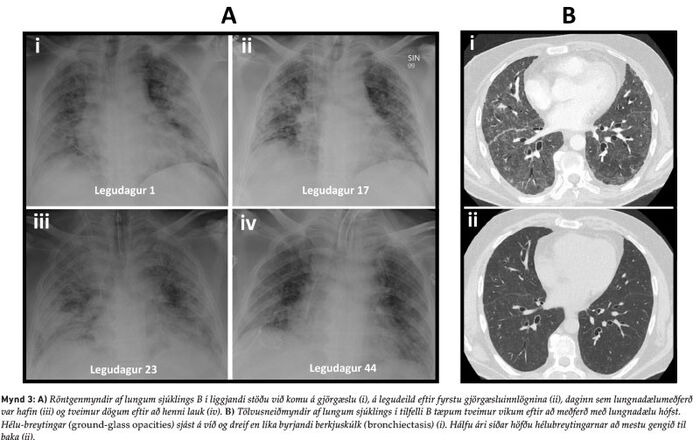

Karlmaður á miðjum aldri, óbólusettur gegn COVID-19, og með sögu um þvagsýrugigt og ofþyngd var fluttur með sjúkrabíl á bráðamóttöku Landspítalans vegna alvarlegrar öndunarbilunar. Hafði hann greinst með COVID-19 sýkingu átta dögum áður. Á bráðamóttökunni mældist súrefnismettun 59% án viðbótarsúrefnis, en hækkaði í 69% með 15L/mín af súrefni á sarpmaska. Hann var fluttur beint á gjörgæslu og gefnir 40 L/mín af 100% innöndunarsúrefni í gegnum háflæði súrefnisgleraugu. Engu að síður náðist súrefnismettun ekki yfir 90% og var því ákveðið að svæfa hann og síðan barkaþræða fyrir meðferð í öndunarvél. Röntgenmyndir sýndu útbreiddar íferðir í báðum lungum (mynd 3A-i). Hafin var meðferð með remdesevír, dexametasón og tocilizúmab, og tveimur dögum síðar var sýklalyfjameðferð með ceftríaxón bætt við, en henni hætt fimm dögum síðar þegar neikvæðar ræktanir lágu fyrir.

Eftir 13 daga meðferð í öndunarvél og 17 daga á gjörgæslu var hann útskrifaður á lungnadeild Landspítala. Þar versnaði honum aftur fimm dögum síðar með háum hita, öndunarerfiðleikum og hækkandi C-reactive prótein (CRP) sem mældist 196 mg/L (viðmiðunargildi < 10 mg/L). Reynd var ytri öndunarvél (bilevel positive airway pressure, BiPAP) með 100% innöndunarsúrefni sem ekki dugði til að halda súrefnismettun yfir 90%. Hann var því aftur lagður inn á gjörgæslu þar sem hafin var innri öndunarvélameðferð og honum síðan komið fyrir í grúfulegu. Röntgenmynd af lungum sýndi auknar íferðir og í berkjuskoli ræktuðust Klebsiella aerogenes og oxacillín-næmur Staphylococcus aureus. Því var ljóst að um var að ræða bakteríulungnabólgu ofan í COVID-19 veirulungnabólgu. Var því cloxacillíni bætt við sýklalyfin meropenem og cíprófloxacín sem hann hafði verið settur á vegna gruns um bakteríusýkingu. Þar sem PaCO2 hélst áfram hátt, eða 127 mmHg, sýrustig í blóði mældist 7,01 og súrefnismettun 88%, var ákveðið að tengja sjúklinginn við lungnadælu. Var það gert á gjörgæslu Landspítala í Fossvogi, enda sjúklingurinn ekki talinn lifa af flutning yfir á skurðstofu Landspítala við Hringbraut. Við lungnadælumeðferðina batnaði ástand sjúklingsins hratt og var henni beitt í samtals 19 daga. Sjúklingurinn greindist þó með Candida albicans blóðsýkingu sem var meðhöndluð með micafungin í æð. Einnig var fleiðruvökvi hægra megin fjarlægður með brjóstholskera. Eftir að lungnadælumeðferðinni lauk, var hann fimm daga til viðbótar á gjörgæslu, og tóku síðan við tvær vikur á legudeild lungnadeildar Landspítalans. Tölvusneiðmyndir sýndu millivefsþéttingar (reticular interstitial infiltrates), hélubreytingar og byrjandi berkjuskúlk (bronchiectasis) (mynd 3B-i) sem að mestu voru horfnar hálfu ári síðar (mynd 3B-ii). Eftir útskrift af Landspítala tók við mánaðar endurhæfing á Reykjalundi og níu mánuðum síðar var hann kominn í fulla vinnu og er við góða heilsu í dag.